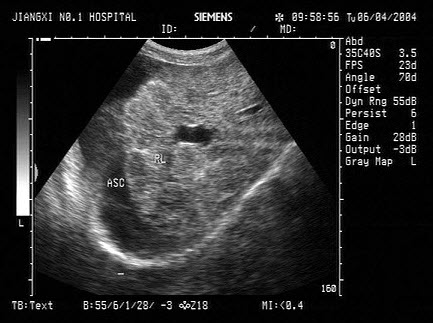

50、单项选择题

男,70岁,上腹胀痛,腹膨隆。脾大,门静脉增宽。结合超声声像图,诊断为()

A.肝血管瘤

B.肝癌

C.血吸虫肝纤维化并腹水